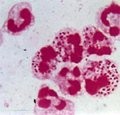

淋病实验室诊断

淋球菌感染的实验室诊断技术主要有:涂片染色直接显微镜检查,观察淋球菌的形态特征;分离培养淋球菌;直接检测临床标本中淋球菌成分如抗原或DNA。1、直接显微镜检查:最常用的方法是分泌物涂片做革兰染色,在光学显微…